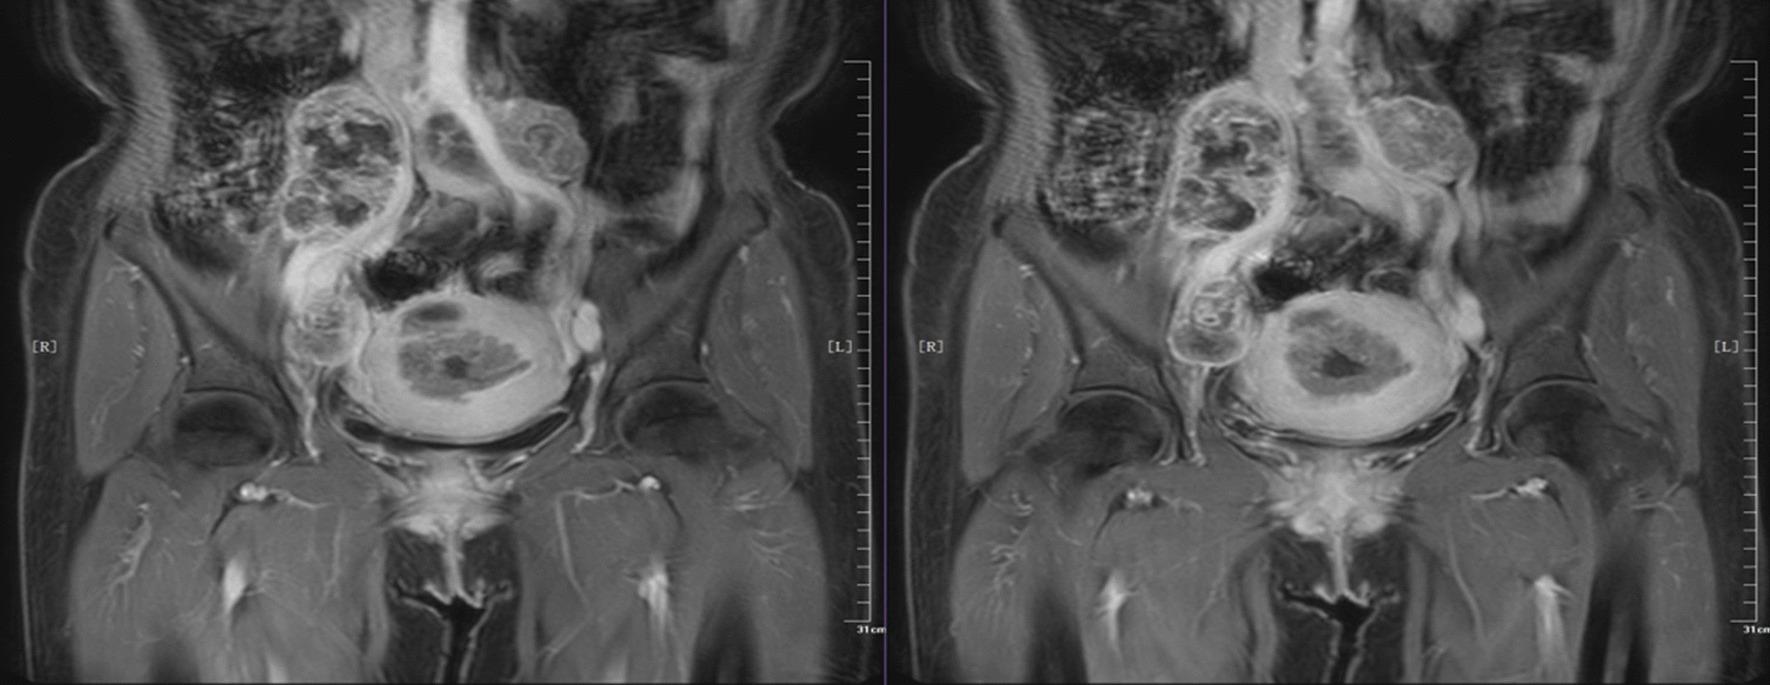

A 54-year-old female patient was first admitted to the hospital in January 2018 due to "irregular vaginal bleeding over 3 months". CT showed a mass in the uterine cavity, and several swollen lymph nodes in the retroperitoneum and pelvic cavity. The initial diagnosis was an endometrial malignant tumor. We performed radical endometrial cancer surgery with parallel resection of inferior vena cava, abdominal aorta, bilateral common iliac arteries, bilateral external iliac arteries, and artificial vessel replacement, which was successful, with good postoperative recovery and no lesion progression at 3 years postoperative follow-up.